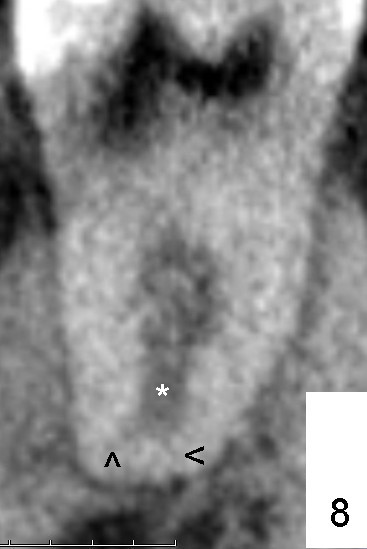

近中根上三分之一好像是单根(图二*以及图一左上),快到中三分之一根管一分为二(图二箭头:B颊侧,L舌侧;图四左上箭头),中三分之一近中舌侧根管仿佛有两个侧枝根管(图五箭头),尽管下三分之一根管又融合(图八*,图七左上横断面:单个扁根管),中三分之一近中两个根管必须分别清洗(图六红色粉红色:两个扩大针),之前应该扩大根管进口(图三A: access,与图二对比)。如果偷懒或者事先无知而遗留一个根管,往后处理并发症可麻烦。本例病人马上要到老美牙学院上学了。

有两个疑问:第一,根尖三角区(delta; 图八)根管(*)似乎又分裂了(箭头),冲洗是不是要达到那里,扩大针是不是要交叉一下(图九)。